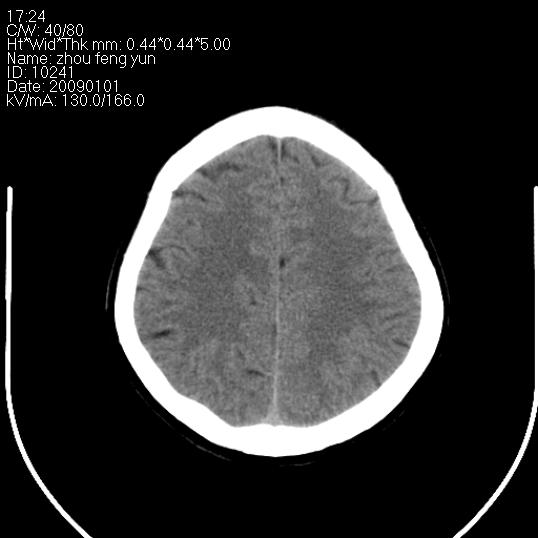

以下是引用hhcckk在2009-1-1 16:39:00的发言:[br]胼胝体嘴、膝部及部分体部发育不全,为囊状影替代,两侧侧脑室分离,脑室后角扩张[br][br]诊断:胼胝体发育不良[br][br]胼胝体发育不良(dysgenesis of the corpus callosum)是最常见的颅脑畸形,是胚胎期背部中线结构发育不良的一种形式。主要包括胼胝体缺如和部分缺如。胼胝体发育不良还可合并其他畸形,如胼胝体脂肪瘤、蛛网膜囊肿、脑膨出、chiari畸形、灰质异位症、脑回畸形等。[br][br]ct诊断要点:[br]1. ct横断扫描可见两侧侧脑室明显分离,脑室后角扩张,形成典型的蝙蝠翼状侧脑室外形。[br]2. 第三脑室扩大并向上插入两侧脑室体部之间,严重者第三脑室可上移到两侧大脑半球纵裂的顶部。在ct冠状扫描位显示更清。[br]4. 胼胝体畸形常伴有脂肪瘤,可测到其特征性脂肪密度。部分脂肪瘤的边缘可出现线样钙化[br]